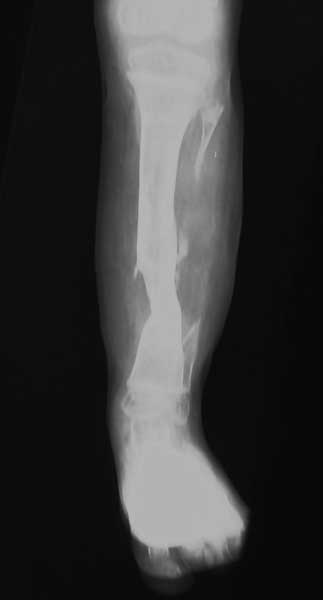

Больной 11 лет. Врожденный ложный сустав нижней трети правой большеберцовой кости.

Больной оперирован неоднократно в областных и республиканских центрах. Прошу о вашей тактике лечения данного больного. Моё мнение: резекция малоберцовой кости в области нижней трети, аккордионной метод компрессии. И дистракция, закрытая кортикотомия верхней трети большеберцовой кости апаратом Илизарова Латиф